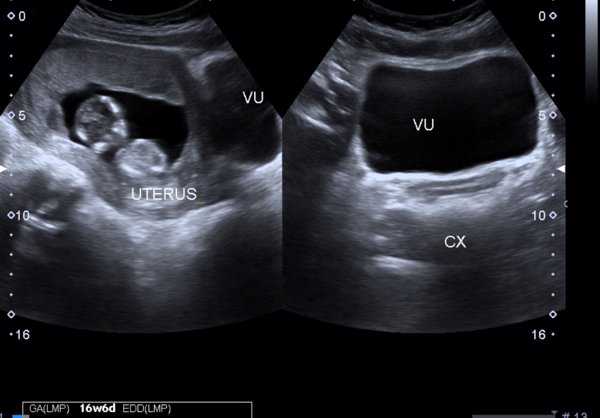

宫外孕通常指受精卵在子宫体腔以外着床发育,此时体内的人绒毛膜促性腺激素(HCG)水平会升高。而正常的宫内孕情况下,HCG值会在一定时间内持续上升,并且数值会高于正常范围。因此,如果在移植后的14天左右进行血HCG值测定,发现其低于正常范围,或者HCG值没有达到预期的增长速度,就有可能是宫外孕的表现。但需要注意的是,这只是一个初步的判断,确诊还需要进一步的B超检查和其他相关检查。

若患者出现腹痛、阴道出血等症状,则可能为宫外孕破裂导致的急腹症,需立即就医处理。